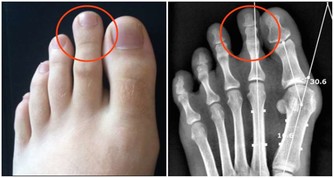

1、關節殘疾

體內的尿酸升高,超出人體承受的範圍,尿酸會形成結晶沉積在關節、皮膚、血管等地方,容易出現炎症。

痛風反復發作導致慢性痛風性關節炎,又會導致發作更加頻繁,間歇期縮短。疼痛逐漸加劇,受累的關節以膝、踝、肘關節多見,嚴重者可累及肩、髖、脊柱,很容易誘發關節的破壞與畸形,導致關節殘疾。

4、痛風石

夏季是痛風“高發期”! 做對5件事,痛風遠離你!

痛風石的形成是長期高尿酸血症引起的組織損傷的結果,是痛風的特徵性病變;沉積在關節囊,影響關節活動;可導致骨“鑿孔”樣損害,嚴重者可導致骨折。關節脫位及畸形;痛風石破潰後,不易癒合,極易導致截肢悲劇。